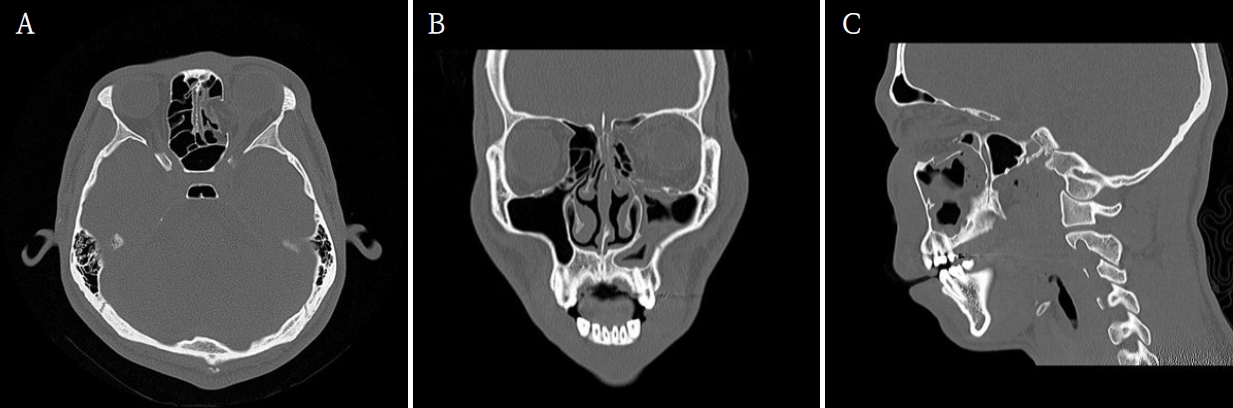

Orbital inferior and medial wall repair via the paranasal sinus: A case report

Jinlee Kim, Haemin Kim, Jaeyoung Ryu, Seunggon Jung, Min-Suk Kook, Chung Man Sung, Hyung Chae Yang, Hong-Ju Park

2025;63(11):353-358. Published online November 30, 2025